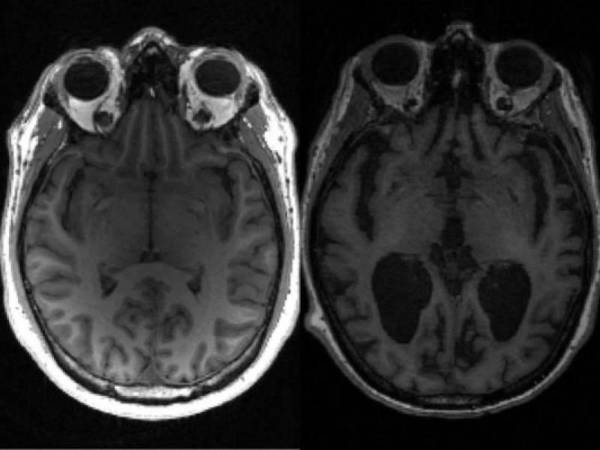

Los niveles altos de un biomarcador clave de la inflamación cerebral podría indicar desde temprano que una persona desarrollará alzhéimer.

Científicos latinos en EEUU hallan un biomarcador que podría detectar temprano el alzhéimer

El estudio, el primero que indaga con detalle cuán pronto empieza a elevarse este biomarcador, "detecta la neuroinflamación que hay en la enfermedad"